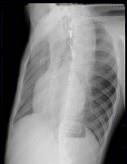

问题 21岁男性患者,劳累后心悸、气促5年,听诊第2肋间有喷射性杂音,胸部三位片如图所示,你认为正确的描述和答案是 ( )

选项 A、考虑房间隔缺损 B、考虑室间隔缺损 C、右前斜位示左心房食管压迹未见明显加深 D、左、右前斜位示右心房段延长 E、后前位示心脏左移,主动脉结缩小,肺动脉段突出

答案 ACDE